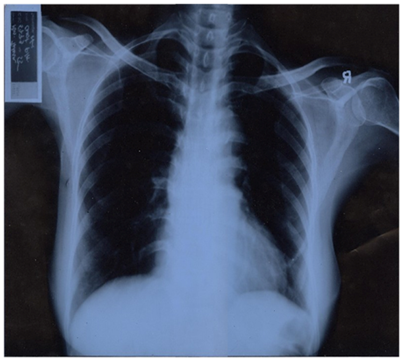

On investigation, her Hb% was 8.7gm%, total count of WBC was 15,000/dl, polymorph was 73% and lymphocyte count was 22%. Urine revealed no abnormality. USG of lower abdomen was done and was reported as normal. Patient was admitted to IBH. After admission she was treated conservatively. On the following day patient had only mild tenderness on the abdomen and discharge from the hospital. On the same night she developed severe pain and was admitted again. She was prepared for emergency appendicectomy. As the patient had complains of amenorrhoea for 3days spinal anesthesia was given. Lanz incision was given and appendix was tired to identify. But after repeated attempt appendix was not found in right iliac fossa. The incision was extended but failed to localize caecum and ascending colon. Some form of congenital anomaly was suspected. General anesthesia was given and the anesthetist identified that her heart beat was on the right side. After confirmation of dextrocardia small gut was followed up and caecum was indentified on the left side. Appendix was found inflamed and appendicectomy was done, recovery of the patient was uneventful. After operation for confirmation of situs inversus chest X ray and USG was done and dextrocardia and situs inversus was confirmed (Figure 1).

Figure 1 CXR – Mrs. Bithi.